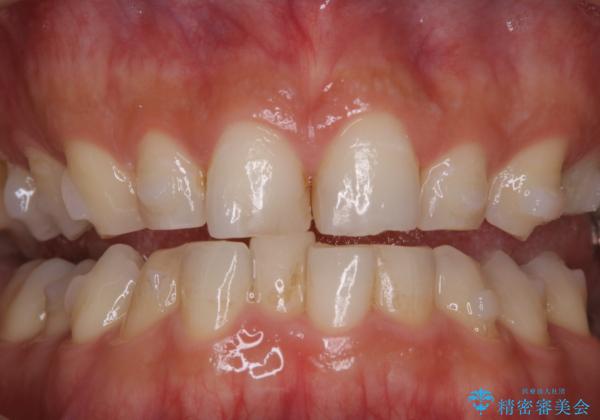

インビザラインでのマウスピース矯正中にPMTCでステインの除去

- インビザラインでの矯正治療中に着色を取るクリーニンングも行いたいとのことでした。PMTC30分コースを行いました。